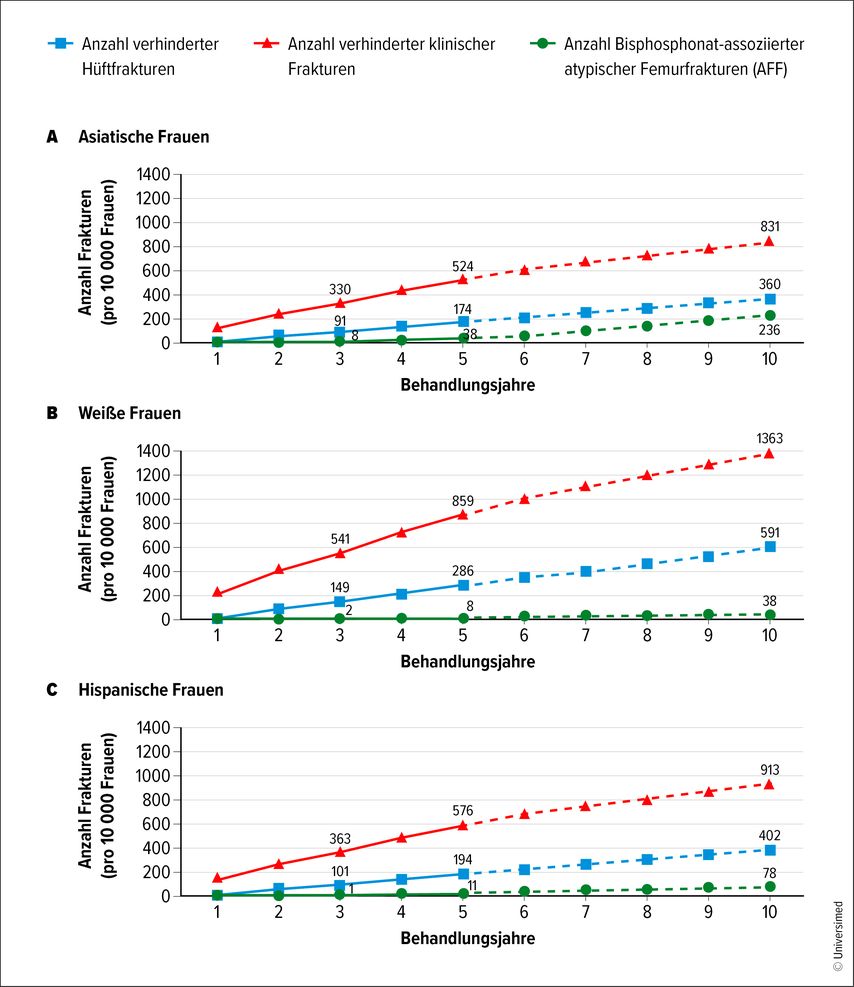

Eine langjährige Therapie mit Bisphosphonaten reduziert zwar das Risiko osteoporotischer Frakturen, erhöht aber das Risiko atypischer Femurfrakturen. Vergleicht man drei Jahre Therapie mit einer Therapie über weniger als drei Monate, ergibt sich eine Risikoerhöhung um mehr als den Faktor 8, bei acht Jahren Therapie ist das Risiko mehr als 40-fach erhöht. Ausschlaggebend ist letztlich die kumulative Bisphosphonatdosis. Weitere Risikofaktoren sind geringe Körpergröße, hohes Körpergewicht, Glukokortikoidgebrauch sowie Gebrauch von Protonenpumpen-Inhibitoren. Im Gegensatz dazu erhöhen Diabetes mellitus und rheumatoide Arthritis das Risiko für atypische Frakturen nicht. Nach dem Absetzen der Bisphosphonate reduziert sich das Risiko rasch. Insgesamt überwiegt der Nutzen der Bisphosphonattherapie das Risiko atypischer Femurfrakturen bei Weitem. Bei drei Jahren Anwendung kommen auf eine atypische Fraktur 75 verhinderte osteoporotische Frakturen. Rintelen: „In anderen Worten bedeutet das, dass atypische Frakturen selten sind, dabei allerdings dramatisch für die wenigen, die davon betroffen sind.“ Und das sind eher jüngere Patient:innen als betagte – während die Inzidenz osteoporotischer Frakturen mit dem Alter stark ansteigt. In asiatischen Populationen ist das Verhältnis ungünstiger, der Nutzen der Bisphosphonate überwiegt aber auch hier das Risiko (Abb. 2).3 Bei einseitigen atypischen Frakturen des Femurs sollte immer auch der andere Femur begutachtet werden, so Rintelen, da auch dort ein hohes Frakturrisiko besteht. Auch atypische Frakturen der Ulna oder der Tibia kommen vor.

Abb. 2: Verhinderte Hüft- und klinische Frakturen im Vergleich zu AFF im Zusammenhang mit Bisphosphonatanwendung. Dargestellt ist die Anzahl der Frakturen in Abhängigkeit von den Jahren der Bisphosphonatbehandlung, aufgeschlüsselt nach ethnischer Zugehörigkeit. Durchgezogene Linien für die Jahre 1 bis 5 weisen auf eine stärkere Evidenzbasis für die Reduktion des Risikos für Hüft- und klinische Frakturen unter Bisphosphonatbehandlung in den ersten 5 Behandlungsjahren hin als für Risikoreduktionen nach 5 Jahren. Modifiziert nach Black DM et al. 20203